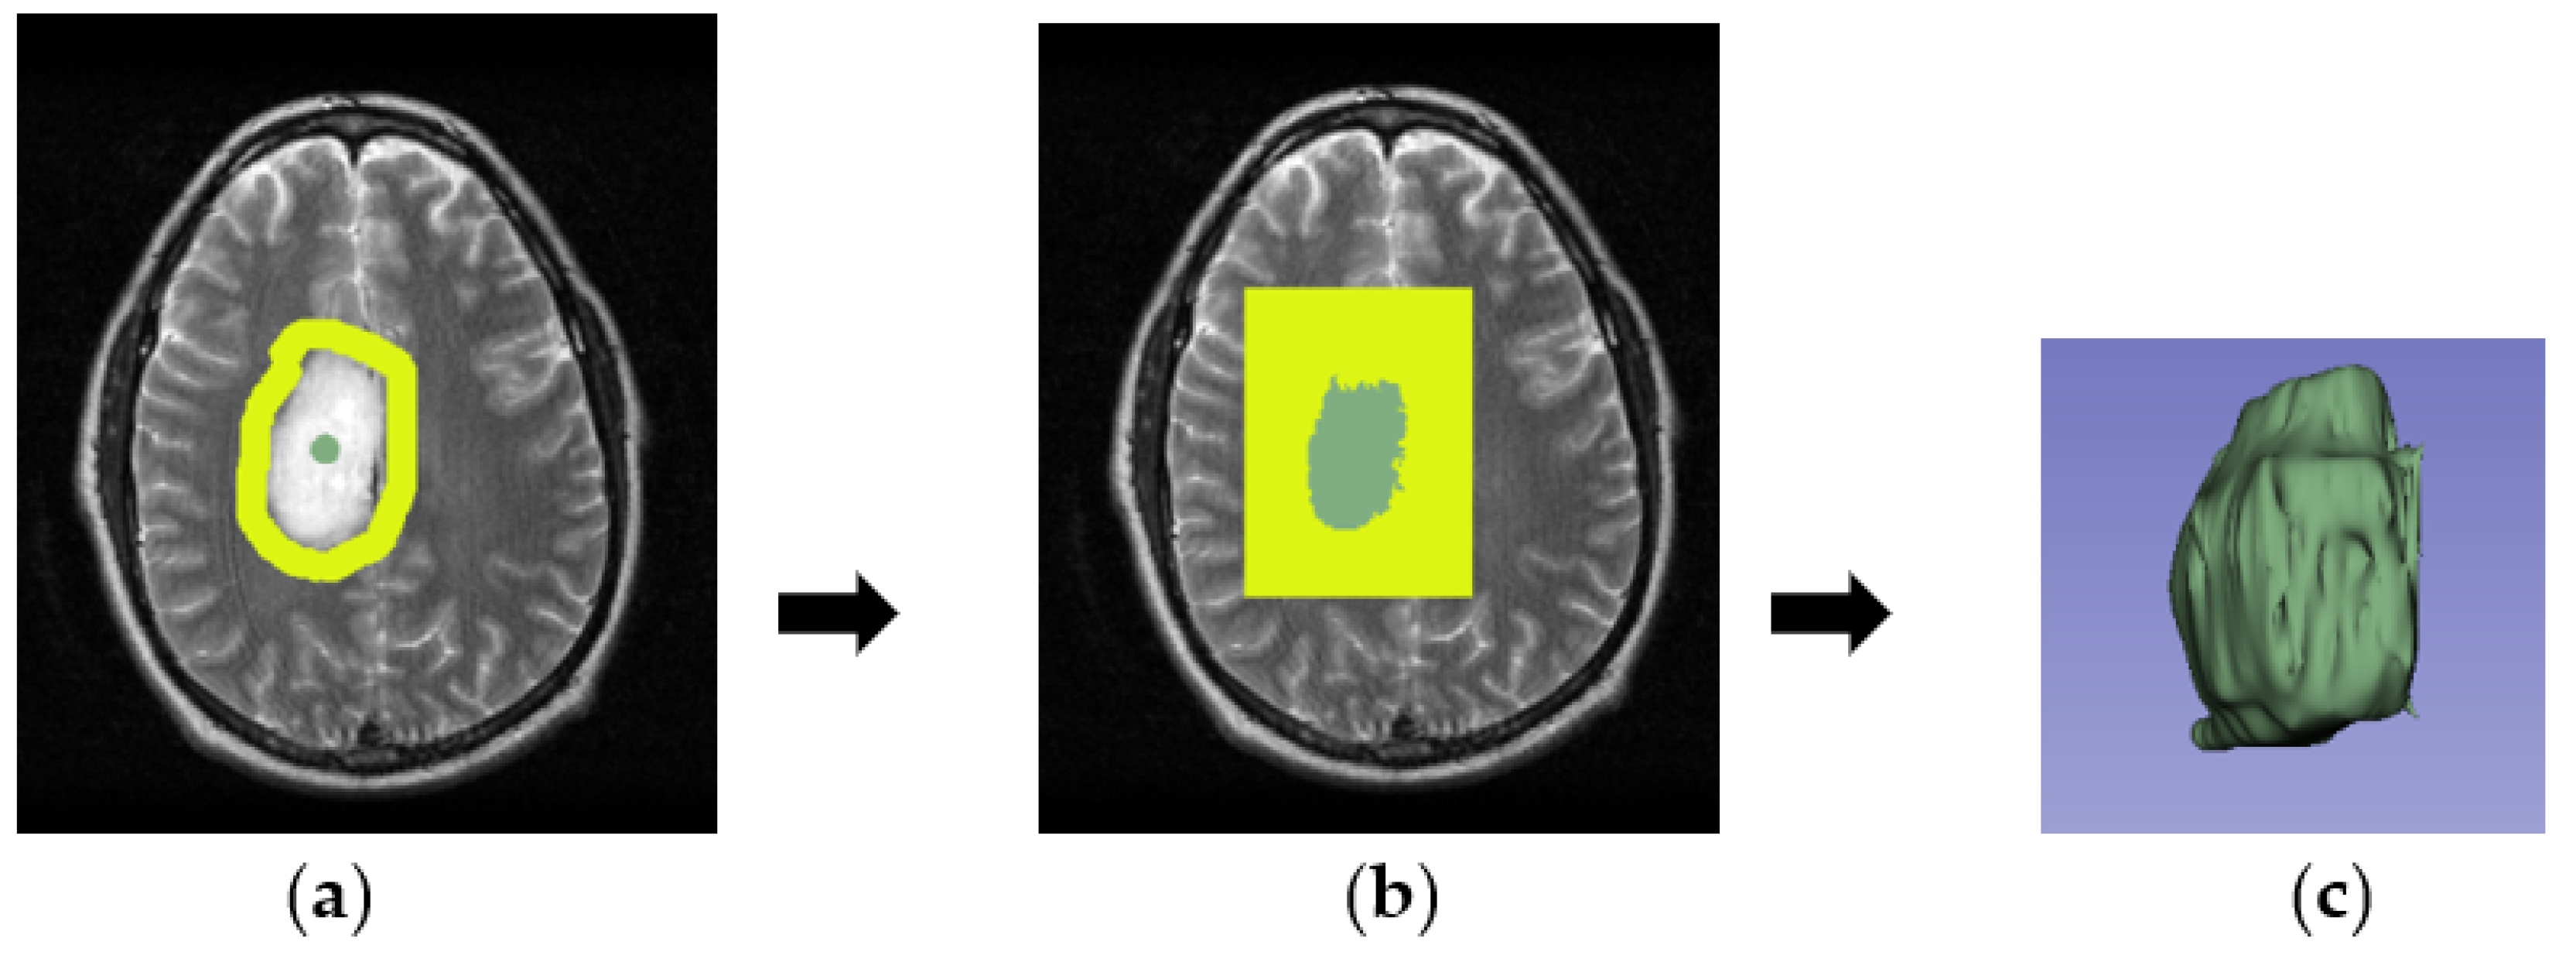

3.2. GrowCut Segmentation